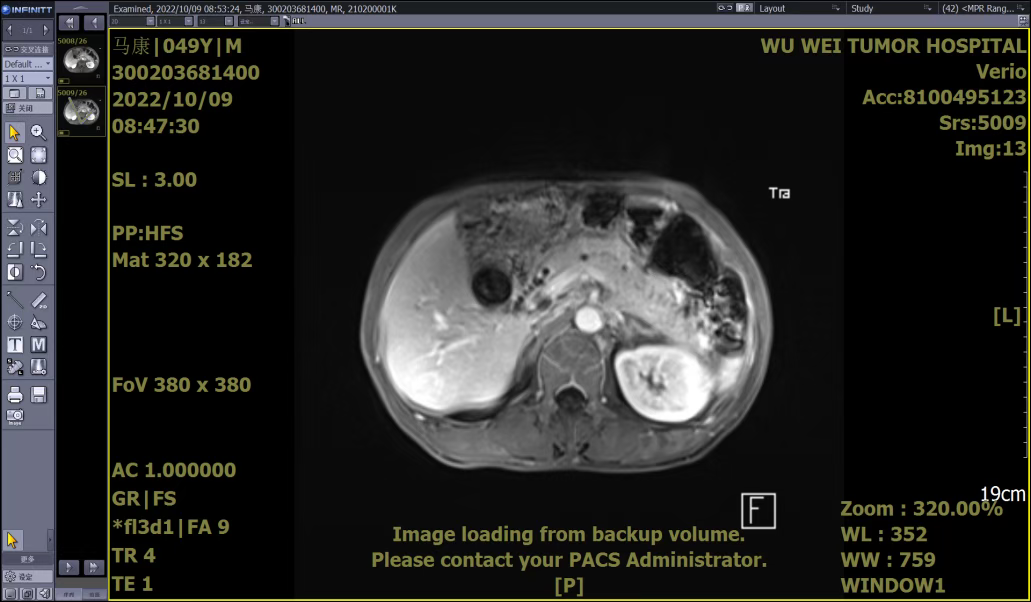

A patient, Mr. Ma, sought medical attention in October 2022 due to "sudden upper abdominal distension and pain for 5 days." Abdominal MRI upon admission indicated: pancreatic thickening with heterogeneous enhancement, reduced enhancement signal in the pancreatic head, enlarged lymph nodes in the portal–caval venous space, suggesting possible tumor. Peripancreatic effusion and pancreatic duct dilation were observed, consistent with acute pancreatitis. Mild intra- and extrahepatic biliary dilation and stenosis of the pancreatic segment of the common bile duct were noted, along with multiple gallstones.

After admission, symptomatic treatments such as anti-infection therapy, enzyme inhibition, and fluid replacement were administered. Endoscopic retrograde cholangiopancreatography (ERCP) with nasobiliary drainage was performed. Endoscopic ultrasound revealed an irregular hypoechoic lesion in the pancreatic head, dilation of the main pancreatic duct, invasion of the pancreatic segment of the common bile duct, and a solid irregular lesion within the duct wall. An enlarged hypoechoic lymph node was observed near the portal vein. Pathological examination of the endoscopic ultrasound-guided pancreatic biopsy showed: (Pancreatic head puncture tissue) blood clot-like material with a small amount of pancreatic tissue, consistent with acute pancreatitis and necrotic changes.

Although the initial biopsy did not support a tumor diagnosis, abdominal MRI and endoscopic ultrasound suggested possible invasion of the common bile duct and enlarged lymph nodes near the portal vein. To avoid misdiagnosis, Spyglass examination was performed. Spyglass choledochoscopy revealed destruction, hyperplasia, and diffuse stenosis in the middle and lower segments of the bile duct, with fragile tissue prone to bleeding. Pathological examination confirmed adenocarcinoma of the distal common bile duct.